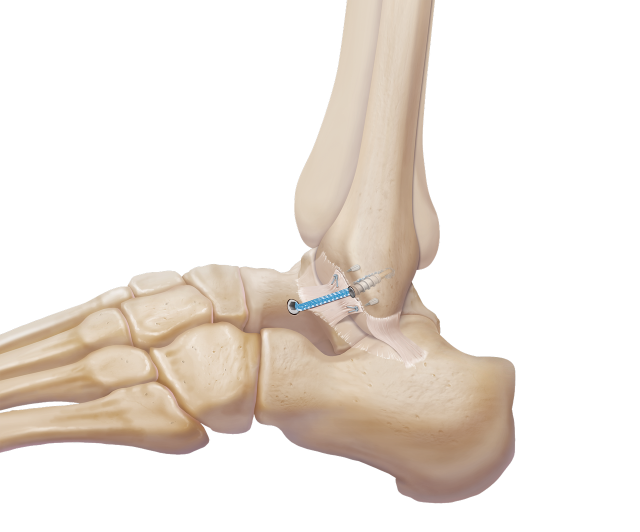

Am Rückfuß sorgen im Wesentlichen vier Bandstrukturen für Stabilität und sichern die regelrechte Funktion des Fußes bei Bewegungen.

Im Zuge von Bandverletzungen kommt es häufig zu begleitenden Knorpelschäden und Sehnenverletzungen und mitunter auch zu knöchernen Verletzungen.

Rekonstruktive Band-Chirurgie